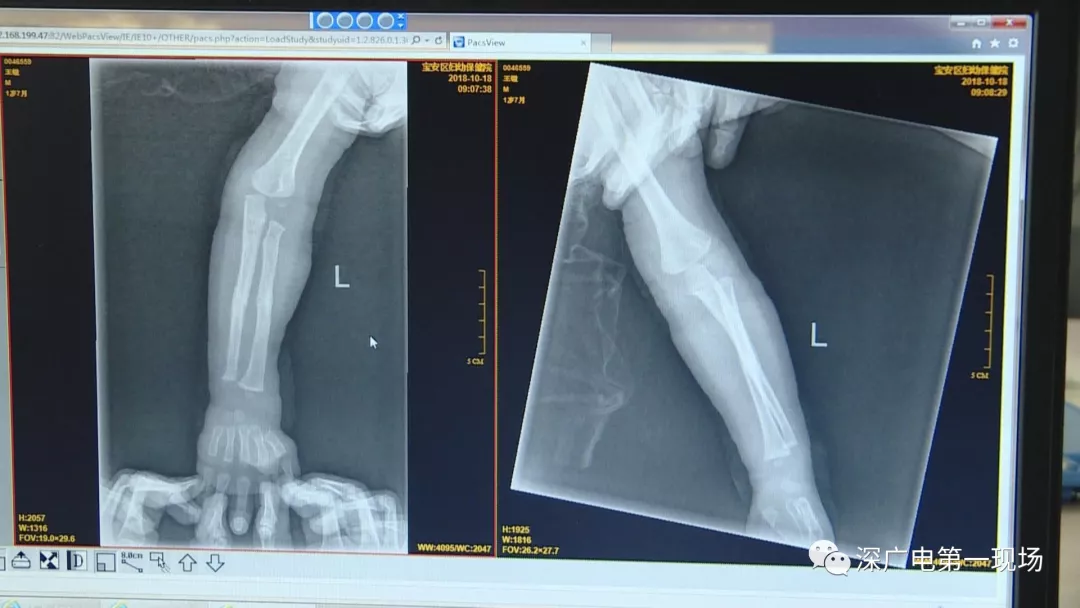

9月4號,一名1歲零5個月的男嬰因在家中摔傷,被父母送到了寶安區(qū)婦幼保健院,醫(yī)生診斷為左側(cè)尺橈骨骨折。在進行全麻手術(shù)之前,院方例行對嬰兒進行了周身檢查。手術(shù)前,兒外科醫(yī)生趙冠聰在查看患者的胸片時,發(fā)現(xiàn)這名嬰兒的胃部有一枚硬幣大小的暗影。